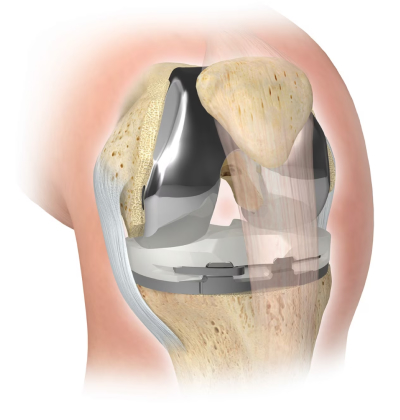

A prótese do joelho nada mais é que um recapeamento da articulação do joelho por implantes metálicos e sintéticos que envolvem os ossos desprotegidos de sua estrutura de proteção nativa (cartilagem). Serve, portanto, para aliviar as dores causadas pela artrose (doença do joelho que elimina / degenera a cartilagem) em condições avançadas. Um joelho que tem artrose avançada dói muito quando usado já que os nossos ossos são vivos e têm nervos que levam o joelho a doer quando perdem sua proteção natural de menisco e cartilagem

Se você imagina o joelho como uma dobradiça tenha certeza de que, na verdade, é muito mais complexo. Para todos os componentes metálicos e sintéticos que constituem a prótese do joelho deve haver uma congruência e similaridade com as superfícies naturais/anatômicas de um joelho normal. Com base na idade, estilo de vida e condições do joelho do paciente, existem diversas opções de design de prótese que podemos escolher para que o paciente possa retomar à sua vida ativa sem complicações. Em última análise, o cirurgião fará uma recomendação do implante (design e marca) com base em sua habilidade e experiência com um dispositivo em particular, bem como suas circunstâncias e necessidades específicas.